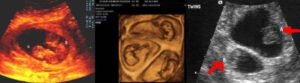

- Дихориальная диамниотическая. Локализация каждого эмбриона определена персональным «детским местом» (плацентой) и амниотическим пузырем. При таком развитии малыши, как правило, разнояйцевые. Двойню видно уже при проведении первого скрининга, начиная с 5–6 недели вынашивания.

- Монохорильная диамниотическая. Эмбрионы располагаются в разных амниотических оболочках, объединенных одним «детским местом». Такую двойню можно увидеть примерно на 9–11 неделе.

- Монохориальная моноамниотическая. Как правило, такую однояйцевую двойню, на УЗИ видно только при втором скрининге. Будущие дети соединены общим амниотическим пузырем и общей плацентой. Это наиболее проблемный вид двухэмбриональной беременности, который тяжело выносить без осложнений.

- УЗИ-диагностика двойни через 11 недель показывает немного уменьшенные для своего срока развития размеры первого и второго плода – примерно 4,2-4,8 см.

- При обследовании на 12 неделе эмбрионы имеют длину по 6 см, а их вес составляет примерно 8 грамм.

- На 20 неделе малыши имеют вес 350 грамм. Можно заметить, что один ребенок крупнее второго. Это происходит из-за кровяного шунта, по которому происходит постоянный сброс крови одному из двух плодов.

- После 32-34 недель малыши набирают вес до 2 кг.